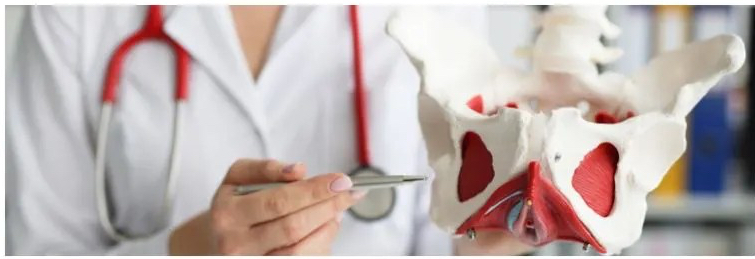

Kiné du périnée

De nombreuses femmes sont confrontées à un moment de leur vie à de l’inconfort liés à la faiblesse des muscles du plancher pelvien. Ces muscles sont souvent fragilisés (grossesses et accouchements, constipation, sport intensif, surpoids, ménopause,… ) et des dysfonctionnements tels que l’incontinence urinaire, les urgences, les prolapsus ou des douleurs apparaissent et ont un impact sur la qualité de vie de la femme.

La rééducation périnéale permet de prendre conscience de ces muscles périnéaux, de les renforcer et de limiter les désagréments lié à leur faiblesse dans la vie quotidienne.